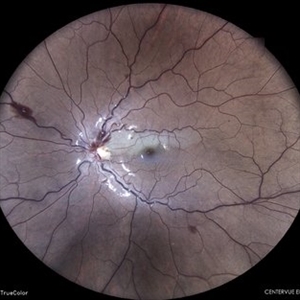

IOL in Vitreous Cavity Right Eye

Fundus infra-red image of a 47-year-old male with IOL in vitreous cavity right eye.

Photographer: Dr. Akansha Sharma-Retina Foundation, Ahmedabad

Condition/keywords: intraocular lens (IOL)